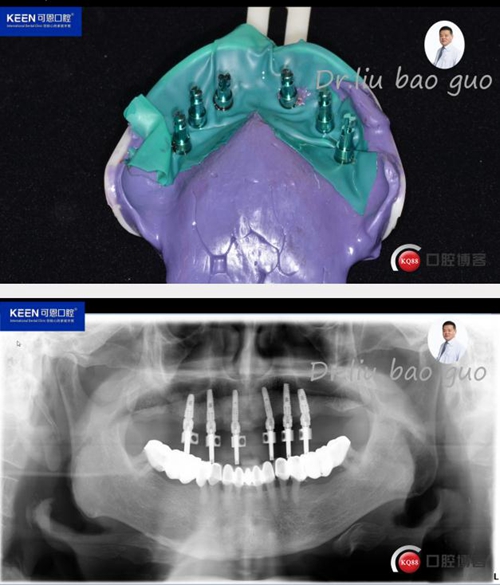

手術(shù)過程

(因設(shè)備限制,未能實(shí)現(xiàn)手術(shù)全程數(shù)字化導(dǎo)板,僅在手術(shù)之前導(dǎo)板定位)

術(shù)后照片

種植后開始進(jìn)行取模,制作義齒